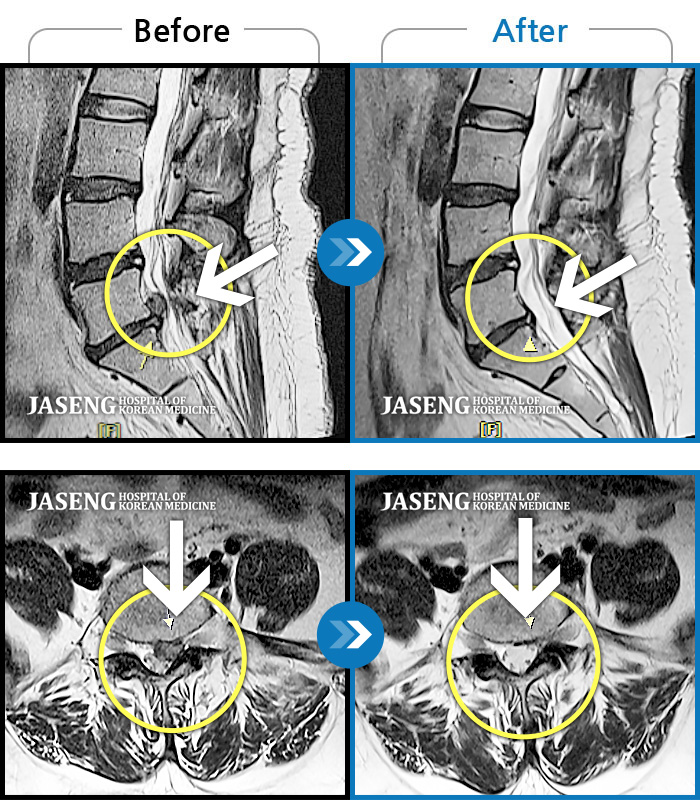

MRI 치료사례

허리 좌측에서 종아리 후면까지 통증, 묵직한 증상